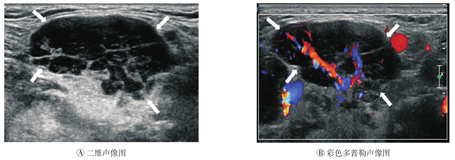

类肿瘤样改变,共7例8灶(36.4%)。病侧腺体长径约2.9~3.7 cm,平均(3.3±0.34)cm,厚径约1.7~2.9 cm,平均(2.4±0.48)cm。腺体饱满、肿胀感;5灶病侧腺体局部隆起,呈分叶状,2灶病侧腺体形态无变化;与周围组织分界清。病侧颌下腺内未见正常腺体回声,显示为回声减低、增粗、不均匀,内夹杂多发条状强回声(图4A),无明显占位效应;腺体内显示放射状分布的丰富血流(图4B)。